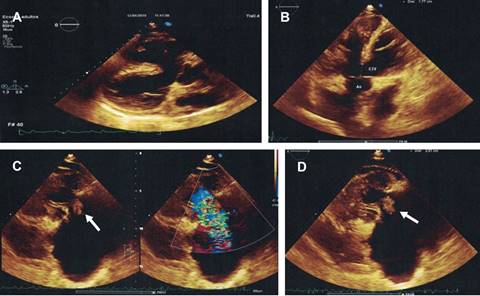

El ecocardiograma (Figuras 3 y 4) evidenció una comunicación interventricular amplia, cabalgamiento aórtico del 50%, dilatación e hipertrofia del ventrículo derecho, vegetación adherida a la superficie auricular de la valva anterior de la válvula tricúspide, que originaba insuficiencia de esta valva, así como estenosis severa de la válvula pulmonar. El hemocultivo reportó Staphylococcus aureus. Por tanto, se estableció el diagnóstico de endocarditis en paciente portador de tetralogía de Fallot. Posteriormente, se inició tratamiento con vancomicina y aminoglucósido endovenosos y se solicitó valoración por cirugía cardiotorácica.

Figura 3: Imágenes del ecocardiograma donde se observa: (A) Comunicación interventricular amplia, cabalgamiento aórtico y dilatación importante del ventrículo derecho. (B) Cabalgamiento aórtico de 50% sobre la comunicación interventricular. (C) y (D) Vegetación grande adherida a la cara auricular de la valva anterior de la válvula tricúspide (flechas) que condicionan una insuficiencia valvular severa.